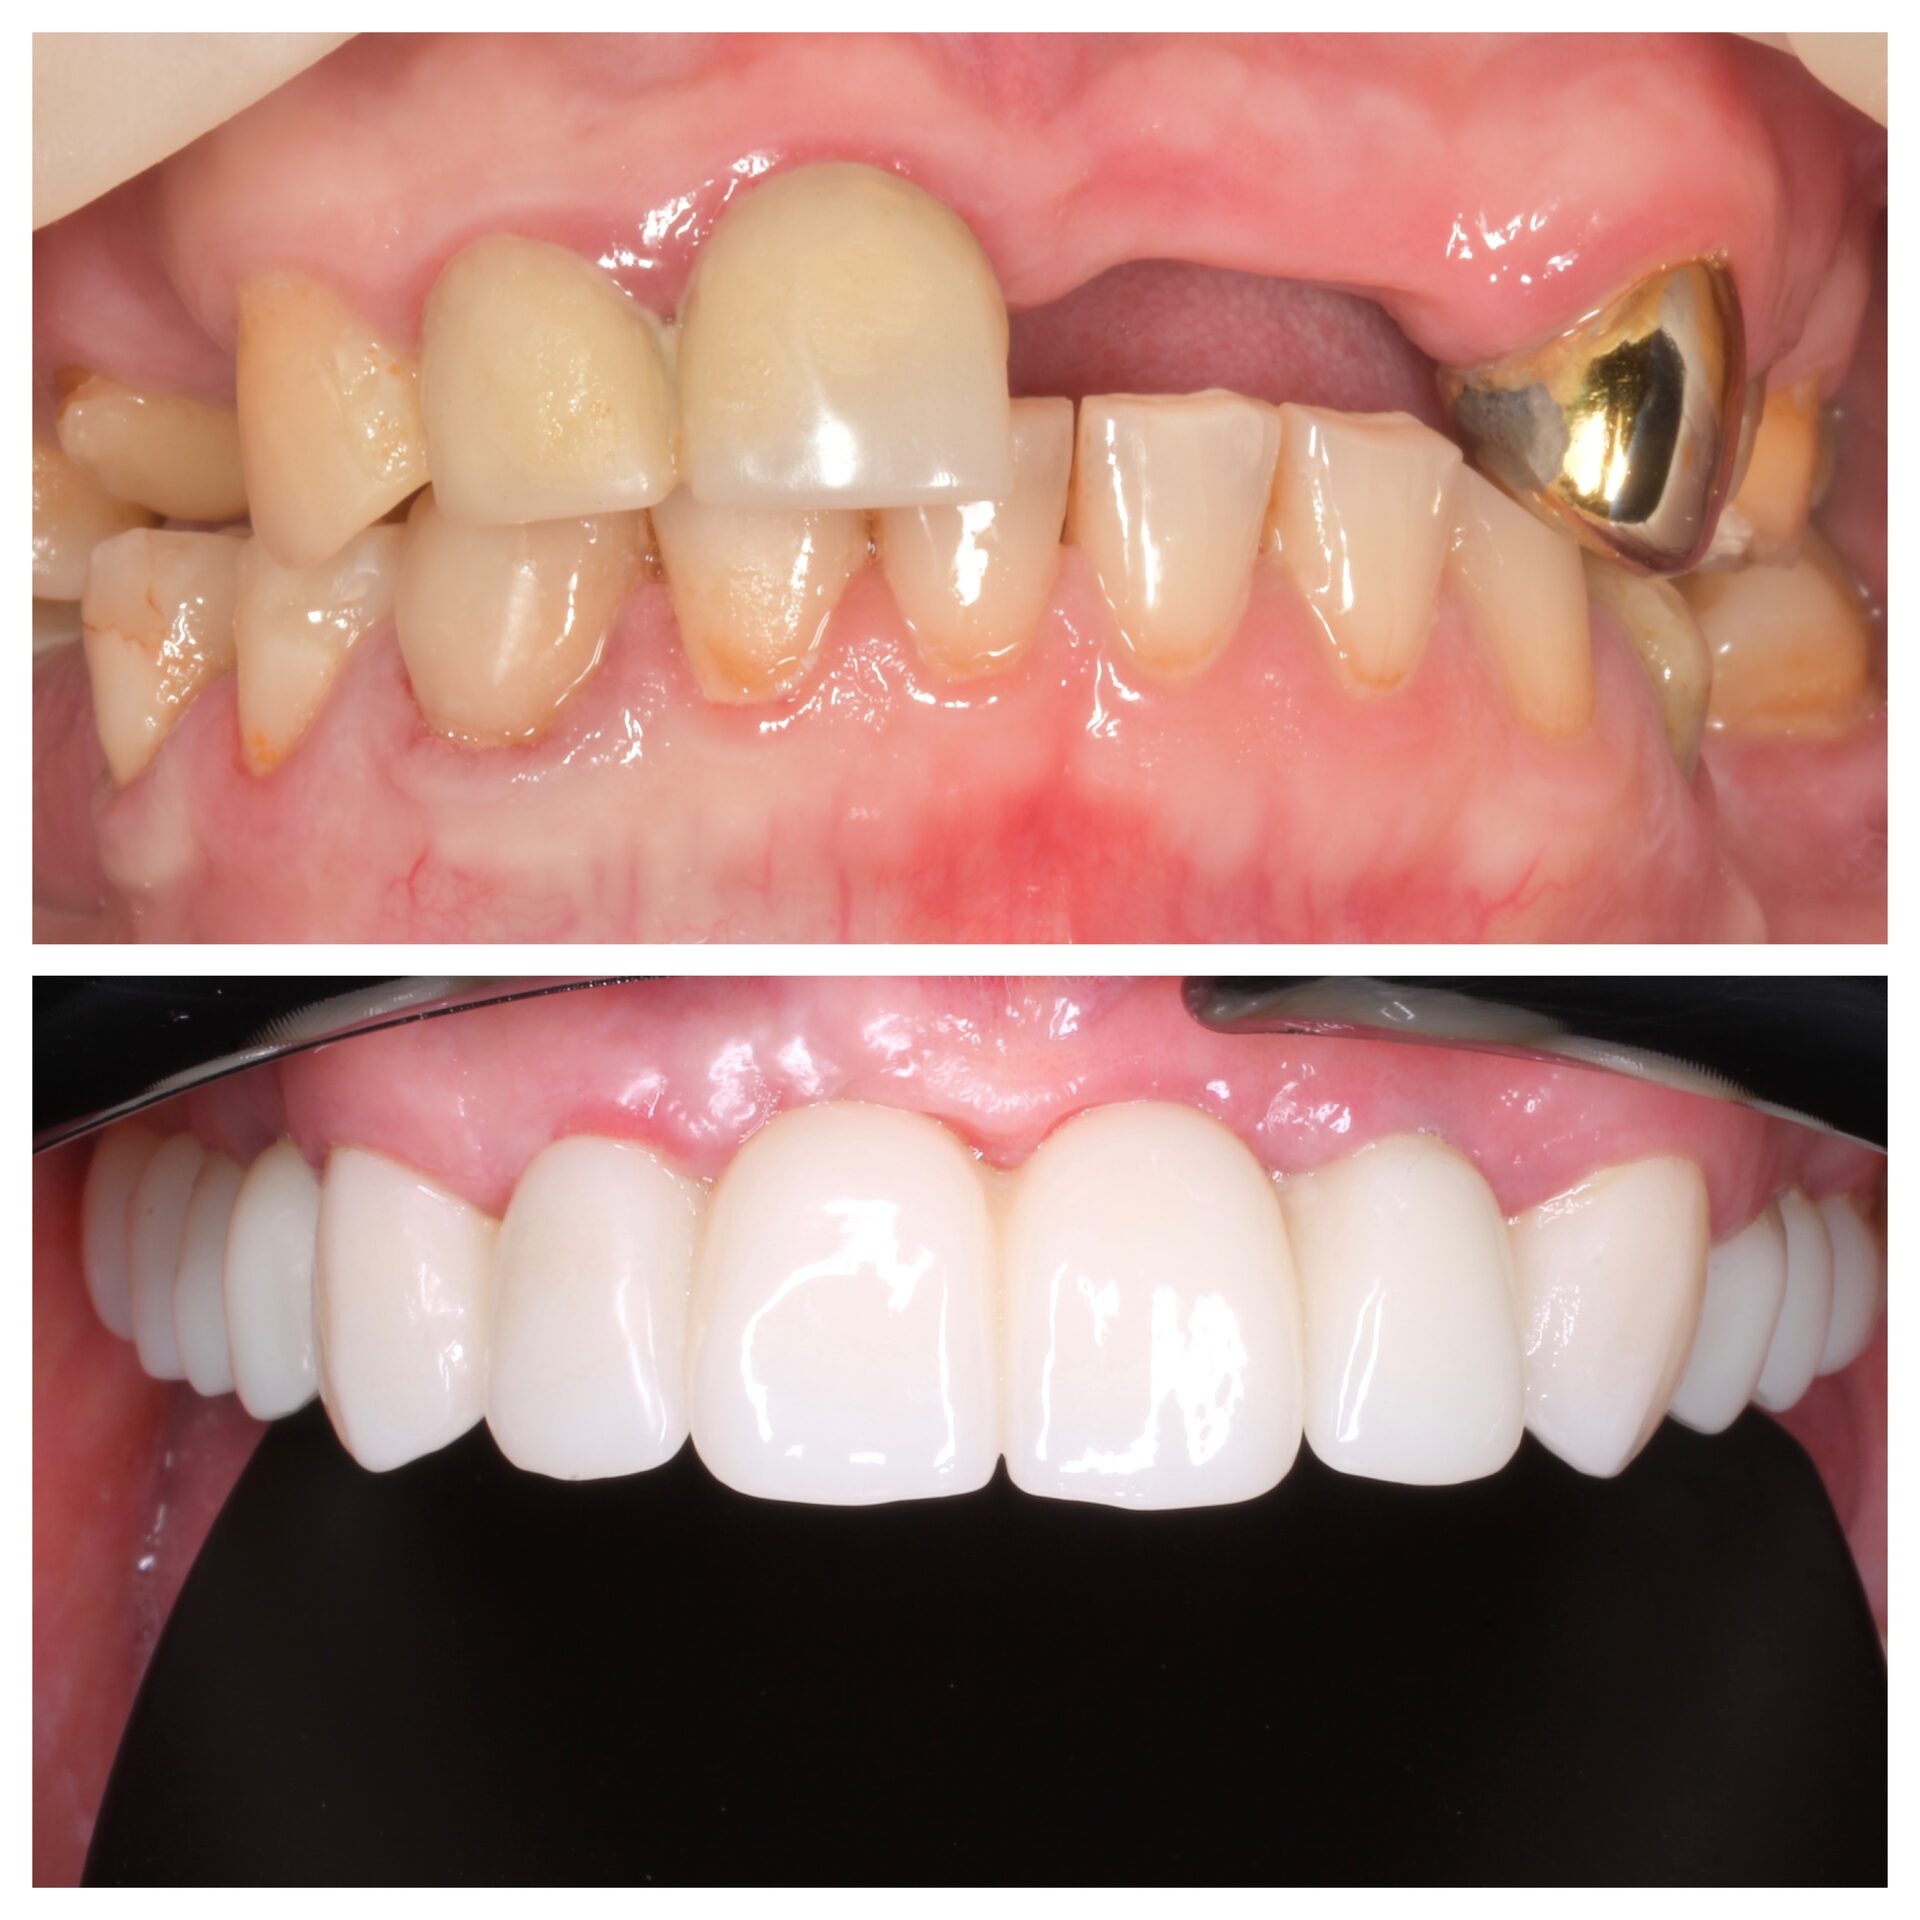

Керамические коронки на имплантате и на своих зубах